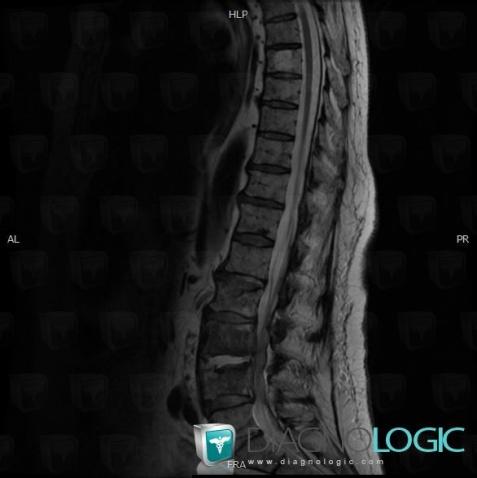

Spondylodiscitis, Vertebral body / Disk, MRI

Here is the specific information in the key image above:

- Diagnosis Spondylodiscitis, Location(s) Vertebral body / Disk, with gamuts

Spondylodiscitis, Spinal canal / Cord, MRI

- Diagnosis Spondylodiscitis, Location(s) Spinal canal / Cord, with gamuts Extradural lesion